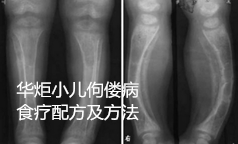

小儿佝偻病食疗配方及方法

佝偻病为婴幼儿时期常见的一种慢性营养缺乏症,主要是因维生素D缺乏而影响钙的吸收,开始表现为患儿烦躁,睡眠不安,夜间惊啼,多汗,后头部秃发。随之出现颅骨软化,头颅畸形,脊柱弯曲,四肢畸形,智力低于正常儿童。重者轻微受伤即易发生骨折。小儿佝偻病属中医五软”“五迟的范畴,先天因素多为父精不足,母血气虚,以致禀赋不足、精气未充、脏气虚弱、筋骨肌肉失其濡养所致;后天因素多为小儿生下后护理不当,或平素乳食不足,哺养失调,或久病体弱,或大病后失于调养所致。中医治疗多从健脾、调肝、益肾入手。